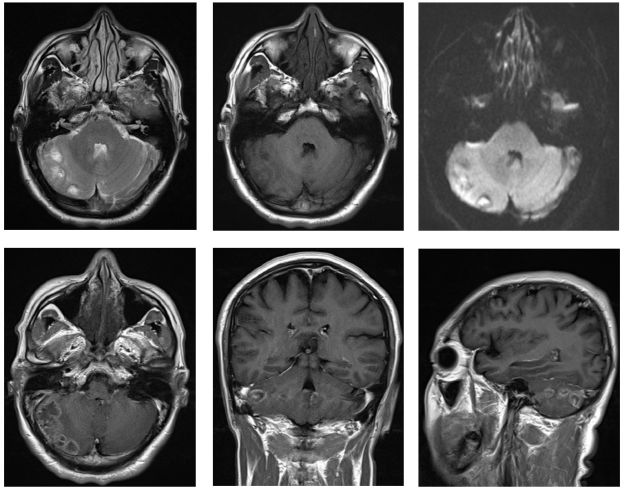

继续抗感染治疗10天,复查头颅MRI提示右侧小脑占位病灶较前增大(图4),提示抗生素对病灶无明显疗效,且血象、CRP、脑脊液相关检查均不支持感染性病变,倾向考虑肿瘤性质病变可能大。排除手术禁忌后,在全麻下行右侧小脑半球病变切除术,术中见病灶为肿瘤,位于右侧小脑半球,色红,质地软,与周围脑组织分界不清,血供丰富,中间伴囊性变,囊液清,呈浅黄色。取少量肿瘤组织(图5),送冰冻提示:小细胞恶性肿瘤,髓母细胞瘤可能。肿瘤予显微镜下全切。术后患者恢复良好,复查头颅MRI提示肿瘤全切(图6),术后一周顺利出院,至放化疗科进一步治疗。

图4. 小脑半球见团片状不均匀长T1长T2信号影,增强扫描可见环形强化,DWI病灶周边轻度受限,周围可见水肿带,占位效应可见,四脑室受压。